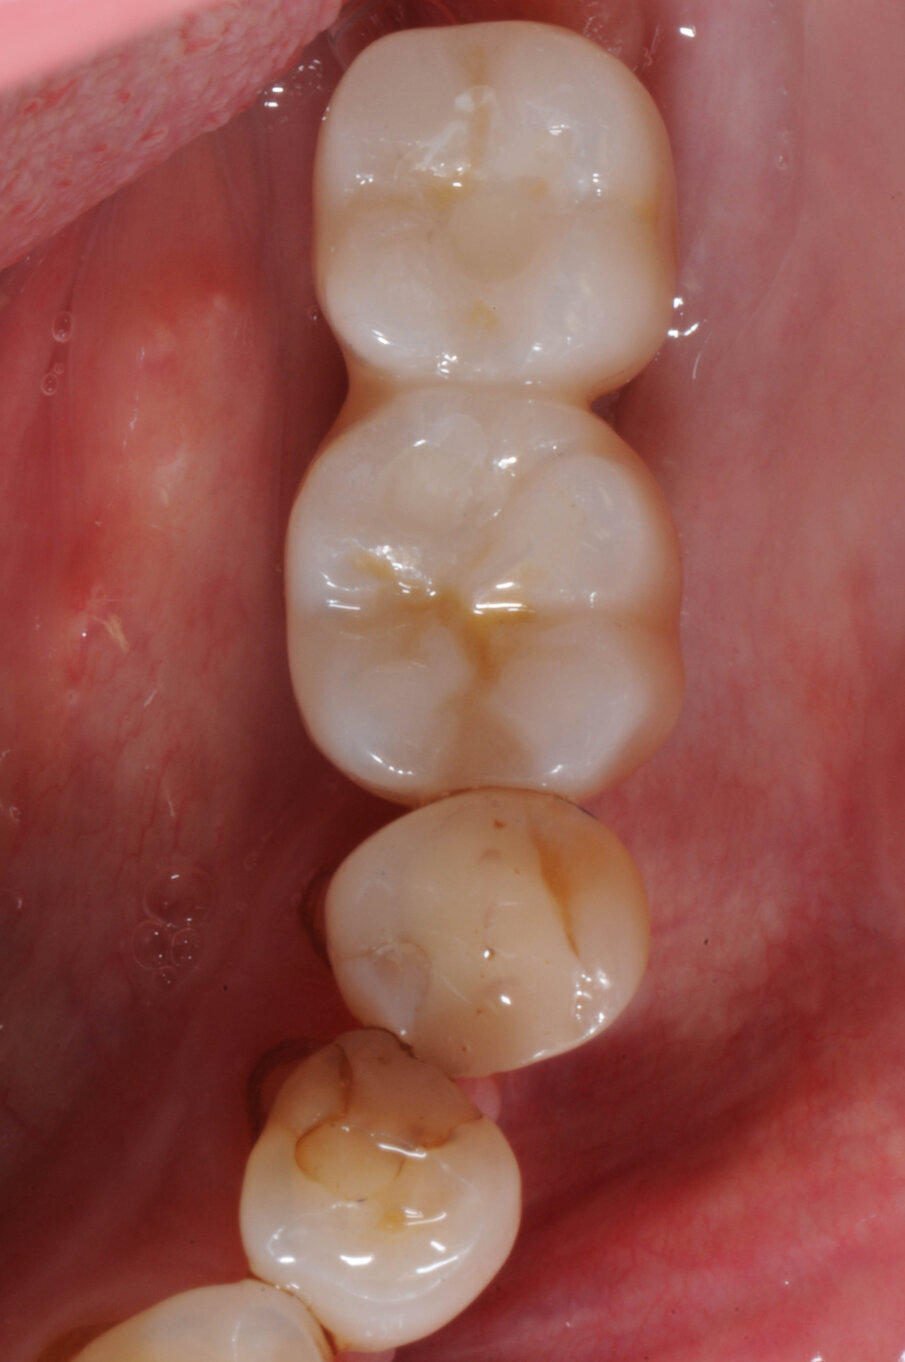

La paziente donna di 72 anni in buono stato di salute generale si presentò alla nostra attenzione per la mancanza dei denti nei settori inferiori posteriori (Fig. 1). Dalla radiografia OPT si notava che nel settore 4 era presente una zona di radiotrasparenza causata dalla recente perdita di due impianti dentali a causa di periimplantite. Si decise pertanto di iniziare a ripristinare il settore 3 (Fig. 2).

Dopo tre settimane i tessuti attorno agli impianti apparivano sani e privi di infiammazione. Era presente anche una banda di tessuto cheratinizzato. Fu presa un’impronta con tecnica del cucchiaio aperto e due settimane dopo furono consegnate due corone in zirconio avvitate. Il controllo radiografico evidenziava una buona stabilità dell’osso crestale (Figg. 10-13).